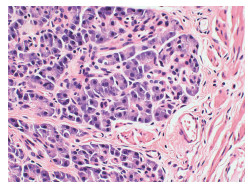

Lymphoepithelioma-like hepatocellular carcinoma: A case report

Xiaotong QIU, Zhengqi WU, Xuxiang XIA, Guoyue LYU

2022, 38(3): 634-635. DOI: 10.3969/j.issn.1001-5256.2022.03.027

Abstract(762) HTML (934) PDF (2924KB)(68)

Abstract: